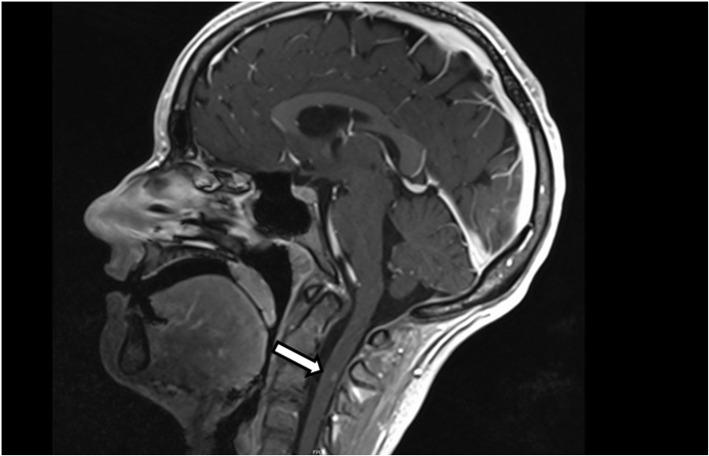

We report a patient with a borderline personality disorder (BPD), which developed NMDAR-E and an overlapping demyelinating disorder with anti-Myelin oligodendrocyte glycoprotein (MOG) -IgG positivity. The initial clinical presentation with predominantly affective symptoms (e.g. mood lability, anxiety, depressed mood) lead us to suspect an exacerbation of the BPD at first. However, acute changes in premorbid behavior, newly developed psychotic symptoms and memory deficits lead us to the correct diagnosis of an AE, which was further complicated by the development of a demyelinating disorder. As a result of impaired illness awareness and psychosis, diagnostic and treatment was difficult to carry out. The symptoms completely remitted after treatment with methylprednisolone 1 g daily for 5 days and 5 cycles of plasma exchange.

我们报告了一例患有边缘型人格障碍(BPD)的患者,该患者发展为 NMDAR-E 和重叠的脱髓鞘疾病,伴抗髓鞘少突胶质细胞糖蛋白(MOG)-IgG 阳性。最初的临床表现主要为情感症状(例如情绪不稳定、焦虑、情绪低落),导致我们最初怀疑是 BPD 恶化。然而,病前行为的急性变化、新出现的精神病症状和记忆缺陷使我们得出了 AE 的正确诊断,随后又并发了脱髓鞘疾病。由于对疾病的认识不足和精神病,诊断和治疗变得困难。经过每天 1g 甲基强的松龙治疗 5 天和 5 个周期的血浆置换后,症状完全缓解。